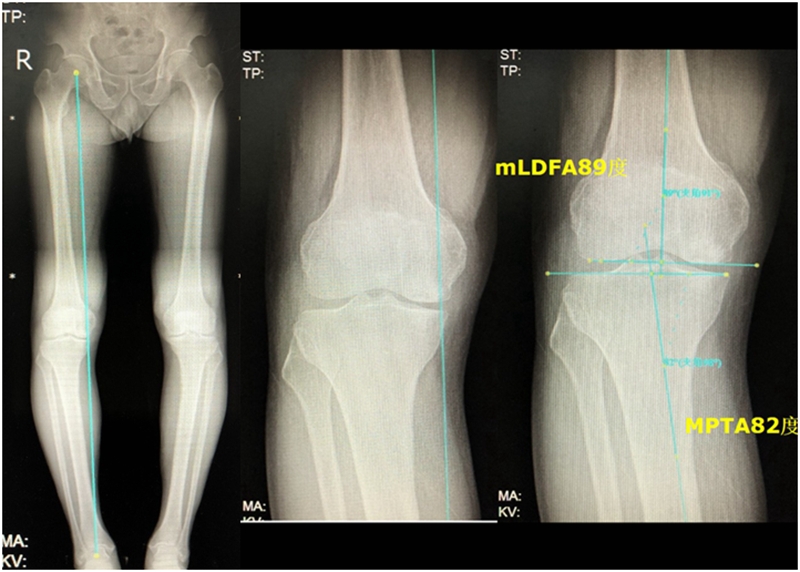

病例1:男,64岁,主诉左膝关节内侧疼痛6年余。MR提示骨坏死区占比为33.28%,矢状位病变区域前后径为26.42mm,半月板相对突出百分比(RPE)31.78%,同时存在胫骨侧来源的下肢内翻畸形(MPTA83°),关节线会聚角2°。

行关节镜检查+软骨摘除+微骨折+HTO术,术后随访2年恢复良好,活动自如,行走时无左膝关节疼痛不适。